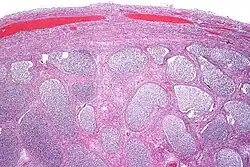

| Acute epididymitis with abundant fibrinopurulent exudate in the tubules. | |